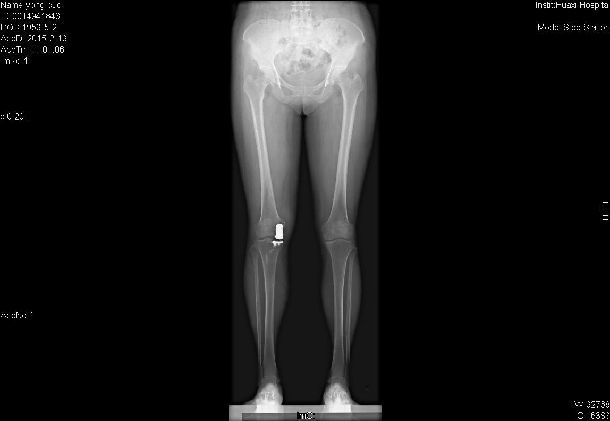

膝關(guān)節(jié)單髁置換術(shù)

膝關(guān)節(jié)包含內(nèi)側(cè)脛股間室、外側(cè)脛股間室、髕股間室。雖然膝關(guān)節(jié)疾病可引起其中任何一個(gè)間室的病變,但臨床研究證實(shí),約1/3的患者的早期病變僅局限一個(gè)間室,以內(nèi)側(cè)脛股間室為主,而其余2個(gè)關(guān)節(jié)間室并未累及。對(duì)于這類病患,采用全膝關(guān)節(jié)置換術(shù)會(huì)令其失去正常關(guān)節(jié)間室的軟骨與韌帶,創(chuàng)傷過大,力學(xué)機(jī)制改變較大。

單髁置換術(shù)適應(yīng)癥:(1)局限于膝關(guān)節(jié)單側(cè)間室的骨性關(guān)節(jié)炎,疼痛嚴(yán)重,需要接受關(guān)節(jié)置換手術(shù)治療;(2)X線征象要求患側(cè)間室關(guān)節(jié)間隙嚴(yán)重變窄,而對(duì)側(cè)間室和髕股關(guān)節(jié)間室保留全層軟骨者;(2)膝關(guān)節(jié)畸形:內(nèi)外翻小于15°,屈曲攣縮不超過15°;(3)術(shù)前膝關(guān)節(jié)屈曲至少 100°的患者;(4)、膝關(guān)節(jié)周圍韌帶結(jié)構(gòu)功能完整的患者。